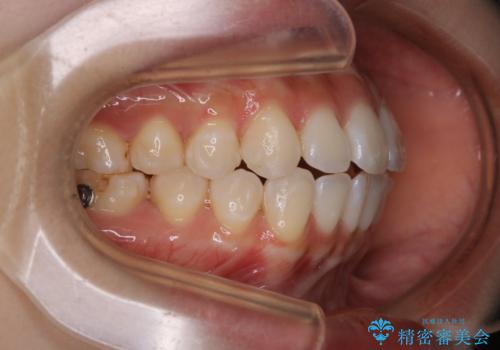

前歯で噛めない:オープンバイト(開咬)を非抜歯インビザラインで治療

- 上下の歯が噛んでいないことを気にしてご相談にいらした方です。

舌癖も認められたため、舌のトレーニングも併せて行い、矯正治療の効率化を図ると同時に後戻りのリスクを最小限に抑えるようにしました。

オープンバイトの方への治療は、通常抜歯を行いワイヤーによる矯正治療を行うことが多いですが、今回はインビザラインの特性を生かし、非抜歯にて綺麗な歯並びを作ることが出来ました。